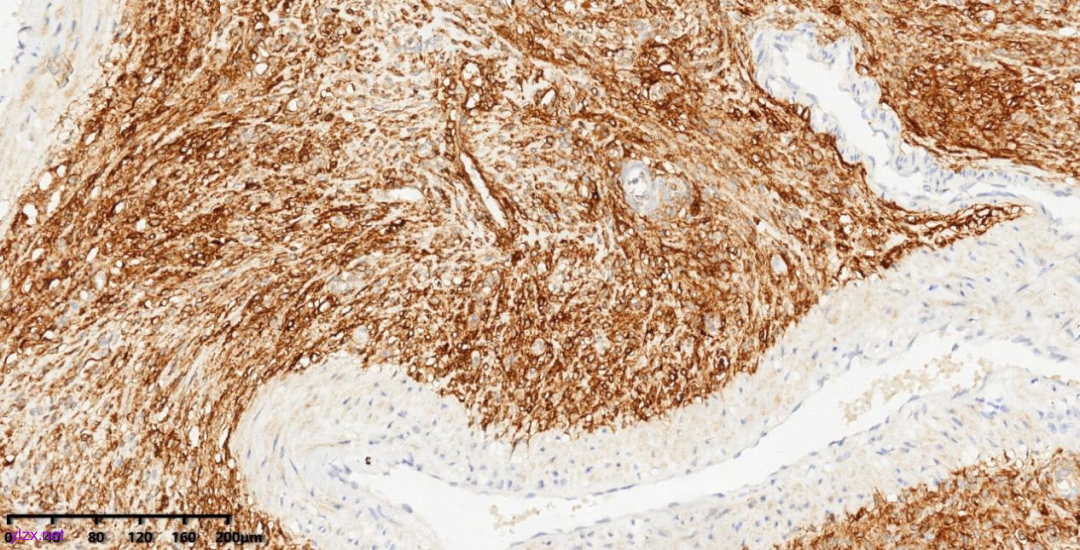

图11 肿瘤细胞HMB45胞浆阳性

图12 肿瘤细胞Desmin胞浆阳性

图13 肿瘤细胞caldesmon胞浆阳性

图14 肿瘤细胞CD10胞浆阳性

图15 肿瘤细胞Ki67增值指数低